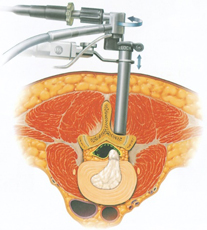

MED法は低侵襲手術として広まっている方法です。手術による傷口は2cm程度と小さい為、身体にかかる負担が小さく、治療に要する入院期間(およそ7日間程度)も短い為、早期社会復帰が可能な手術です。手術方法には腰椎椎間板ヘルニアに対するMED法(内視鏡下腰椎椎間板摘出術)、腰部脊柱管狭窄症や腰椎変性すべり症に対するMEL法(内視鏡下腰椎椎弓切除術)があります。

MED法の応用として腰部脊柱管狭窄症でも除圧できます(MEL法)

反対側の除圧をしています

内視鏡手術(MEL法)で術後脊柱管を拡大したところ